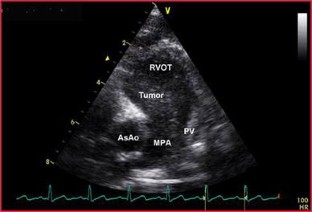

Fibroma, the second most common tumor in childhood, usually is a large solitary mass involving the ventricular septum or the left and rarely the right free ventricular wall. An unusual case of a 5.2-year-old boy with a large mass originating from the pulmonary valve is reported. The patient presented for evaluation of a murmur. Echocardiography and cardiac magnetic resonance imaging showed a large tumor extending from the distal right ventricular outflow tract through the pulmonary valve and into the main pulmonary artery causing moderate obstruction. The patient had a fatal cardiac arrest while awaiting surgery. The postmortem examination proved the tumor to be a fibroma.

Fig. 2